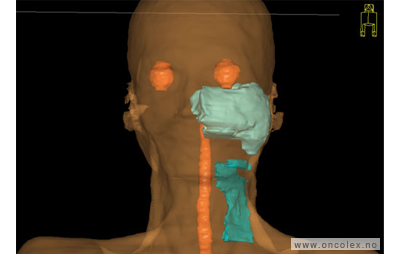

Skisse over hvordan strålefeltet planlegges:

Illustrasjon for målvolum

• GTV (Gross Tumor Volume): Identifisert tumor.

• CTV (Clinical Target Volume) GTV + omkringliggende vev hvor det kan væremikroskopisk spredning.

• ITV (Internal Target Volume): CTV + en indre margin som tar hensyn tilindre bevegelser og endringer av CTV.

• PTV (Planning Target Volume): Innstillingsmargin som inneholder ITV og samtidig tar hensyn til antatte pasientbevegelser, samt variasjoner i pasientopplegging og feltinnstillinger.

• Feltgrense. Tegnes som oftest på kroppen.

ICRU (International Commission on Radiation Units and Measurements)